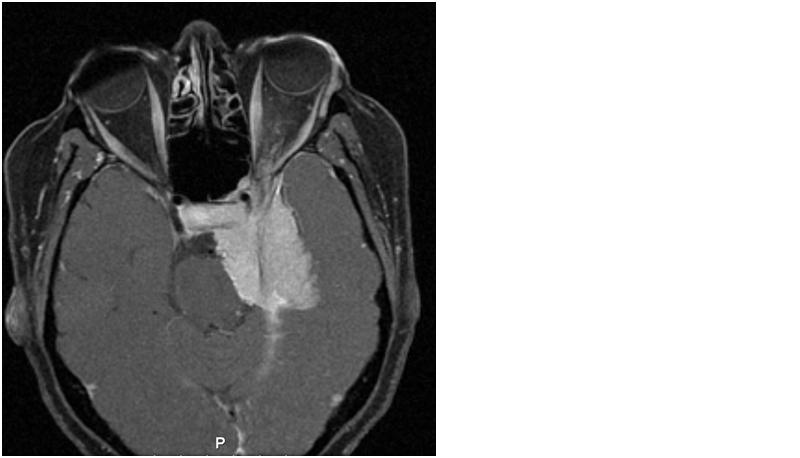

FIGURE 5: Axial T1 post gadolinium MRI image showing a diffuse sphenoid wing meningioma involving the left orbital apex, and cavernous sinus exerting a mass effect on the pons and orbital structures. The image shows the typical appearance of meningioma signified by thickening with sparing of adjacent anatomical structures, as well as exhibiting prominent contrast enhancement and a dural tail.